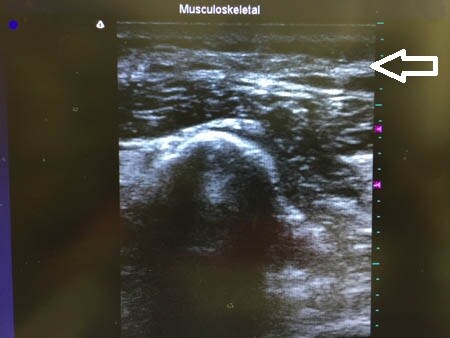

同様に右二の腕。 ↓ ↓ ↓

↓ ↓ ↓